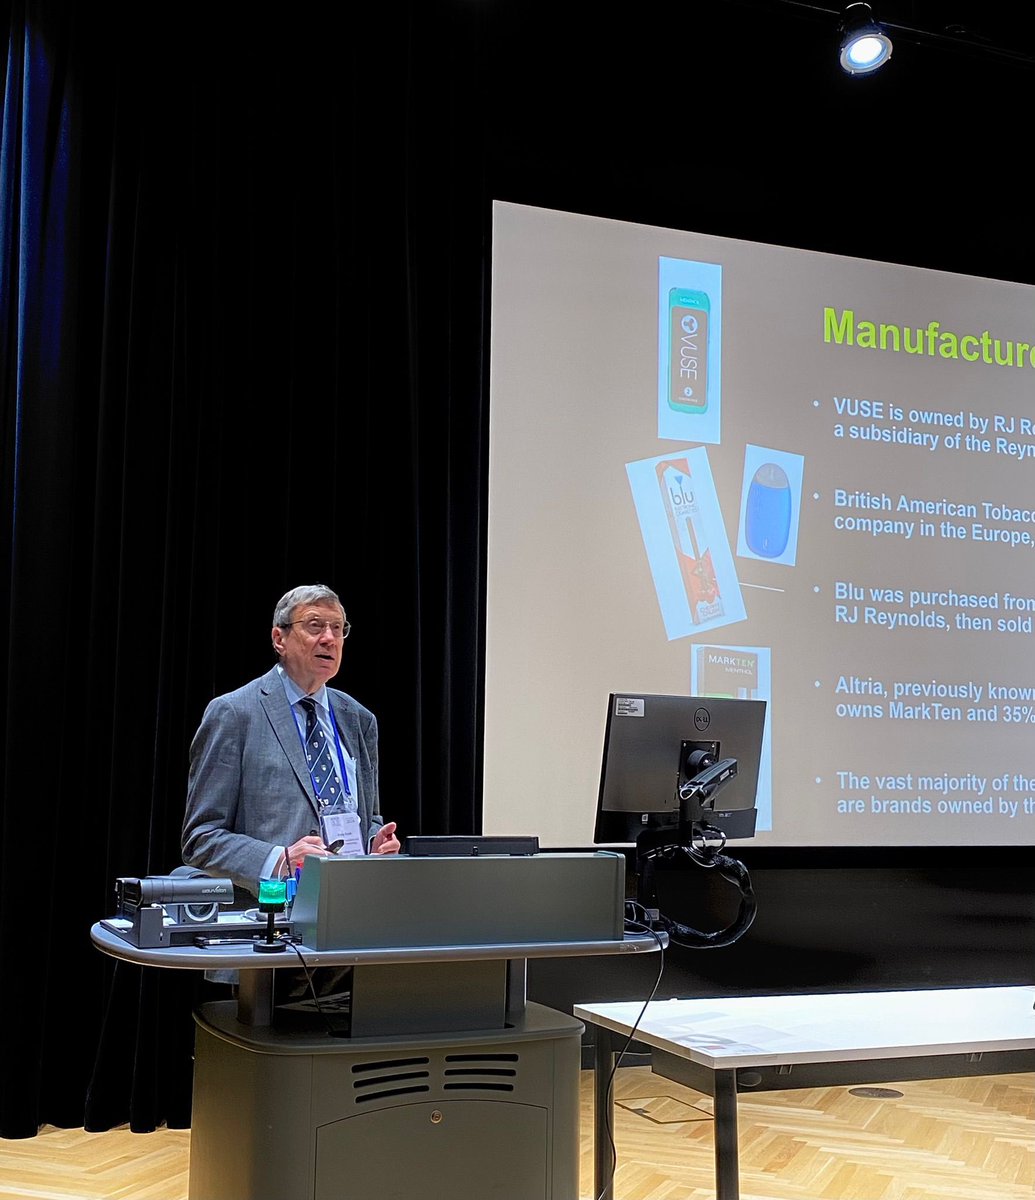

With the UK having one of the highest mortality rates in Europe in CYP with asthma, Dr Mark L Levy will be joining us to further shed light on how we can tackle this largely preventable issue #paedresp2024 #asthma